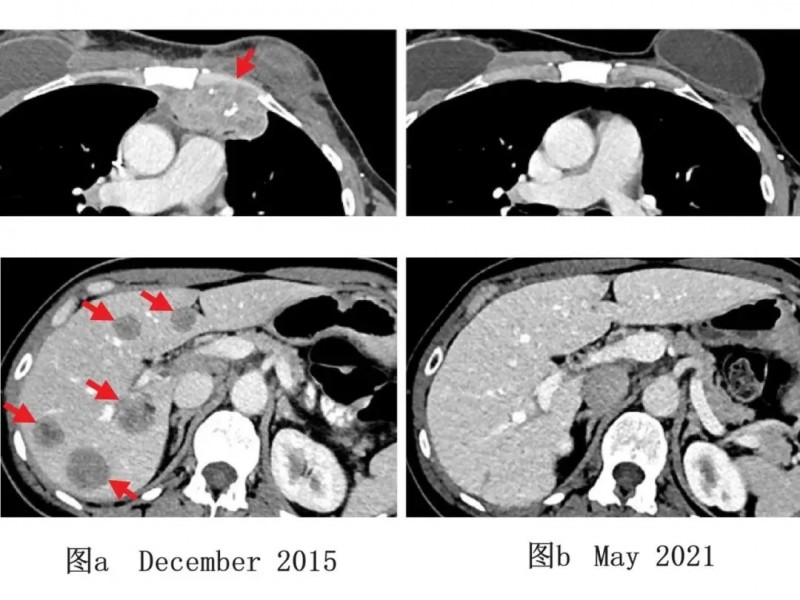

1例乳腺癌典型病例TIL治疗前后的影像学对比图,更是直观印证了治疗效果:2015年12月检查显示,该患者肝脏及胸壁存在转移性病灶(详见下图a);经该免疫联合治疗后,2021年5月影像学检查证实肿瘤完全消退,且5年随访期间未出现复发(详见下图b)。该研究为转移性乳腺癌的免疫联合治疗策略提供了关键临床依据。